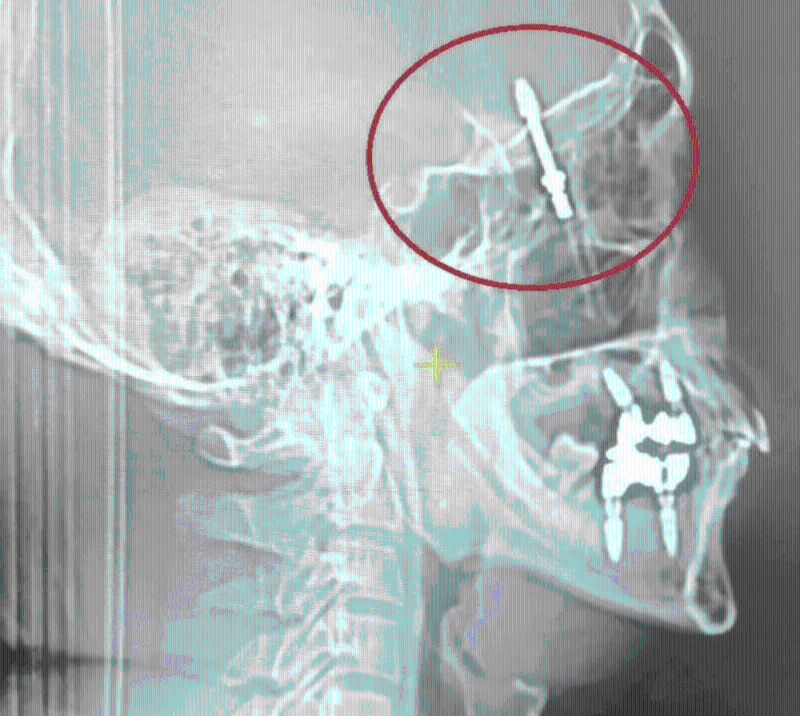

▲一根螺丝钉插穿男子的颚骨和头骨,直达大脑区域。

医生继续用力的转动螺丝,“螺丝就刺穿了我的颚骨,进入眼睛后面大脑和脊随液所在的区域”,他当场痛楚难当。据报,那颗螺丝钉直嵌入拉马赞的大脑中,牙医告知助手,手术中使用的设备坏了,随即为他拍了一张X光照片,并意识到问题的严重性后,马上将拉马赞送医院救治,然后自己便离开。